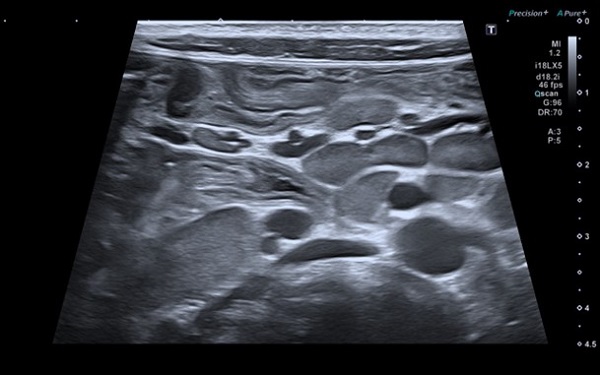

Se completó el estudio etiológico con diversas pruebas complementarias. En la ecografía intestinal inicial se observó engrosamiento difuso de asas, sin claros estigmas de afectación estructurada y adenopatías de carácter reactivo (Figura 1). En el TC abdominal, los hallazgos fueron muy similares (Figura 2). El estudio microbiológico resultó negativo. Para esclarecer el proceso, se realizó una endoscopia alta y baja, macroscópica e histológicamente normales, salvo una atrofia vellositaria total en el duodeno, sin datos de inflamación crónica ni de apoptosis.

| Figura 2. Paciente de 8 años. Crisis celíaca. TC abdominal: engrosamiento difuso e inespecífico de asas intestinales, sin datos de obstrucción/estenosis |

El desafío suele estar en el diagnóstico diferencial, ya que, como se ha comentado, en muchos casos es la CC es la primera manifestación de esta enfermedad. Además, la CC comparte expresión clínica con otros cuadros, tales como una enfermedad inflamatoria intestinal (EII) o una enteropatía autoinmune4. En nuestro caso, y pese a no existir afectación estructurada de asas intestinales en la ecografía, nos vimos en la obligación de realizar un estudio endoscópico completo. Los hallazgos histológicos nos permitieron excluir tanto la EII como la enteropatía autoinume.